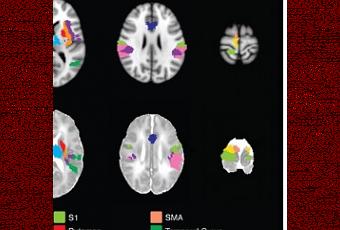

Si la douleur de l’Enfant peut aujourd’hui être évaluée par les professionnels à l’aide d’échelles d’évaluation basées sur ses manifestations cliniques, cette étude de l’Université d’Oxford, menée via IRM, permet aux professionnels comme aux parents de mieux comprendre comment les bébés ressentent la douleur. Les conclusions, présentées dans la revue eLife, confirment qu’il est possible de détecter la signature neurologique de la douleur de l’enfant, comme celle de l’adulte, en utilisant l’IRM (Visuel de droite). Cependant, si approximativement les mêmes zones » s’allument » dans le cerveau de l’enfant vs le cerveau adulte, le seuil de la douleur est beaucoup plus faible chez l’enfant (Visuel de gauche). Des implications évidentes alors que des milliers d’enfants subissent des interventions douloureuses chaque jour.

· 18 des 20 régions cérébrales réactives à la douleur chez l’adulte réagissent également chez le petit enfant,

· le cerveau des bébés répond avec globalement la même intensité que celui de l’adulte exposé à un stimulus 4 fois plus intense, ce qui signifie une bien plus grande sensibilité à la douleur chez l’enfant.